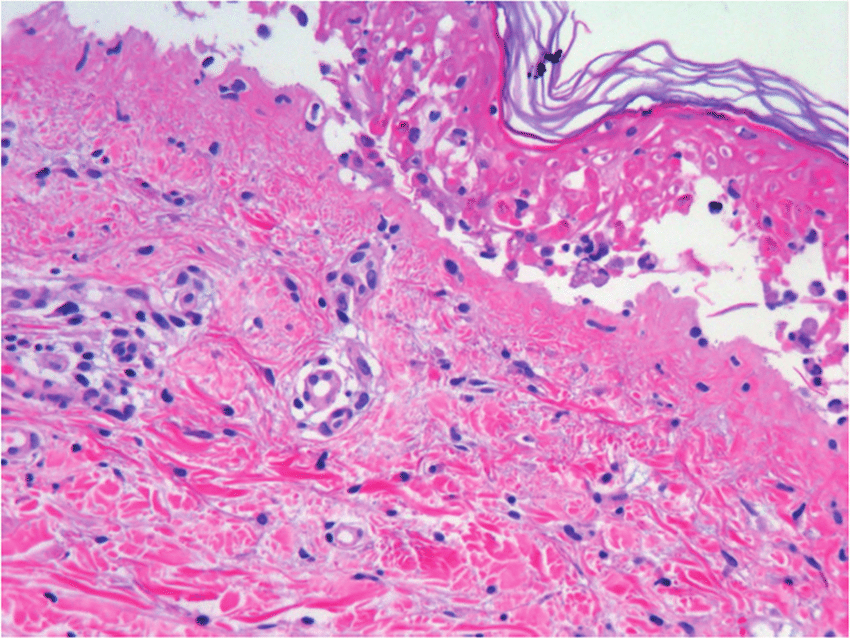

En esta revisión sistemática y metanálisis de todas las series de casos, los antibióticos se asociaron con más de una cuarta parte de los casos de síndrome de Stevens-Johnson y la necrólisis epidérmica tóxica descritos en todo el mundo. La clase de sulfonamida se asoció con el 32 % de los casos, seguida de las penicilinas (22 %), las cefalosporinas (11 %), las fluoroquinolonas (4 %) y los macrólidos (2 %). Estos hallazgos resaltan la importancia de la administración de antibióticos, la educación y la concientización de los médicos, y sopesar la evaluación de riesgo-beneficio de la elección y duración de los antibióticos. JAMA Dermatol. 15 de febrero de 2023